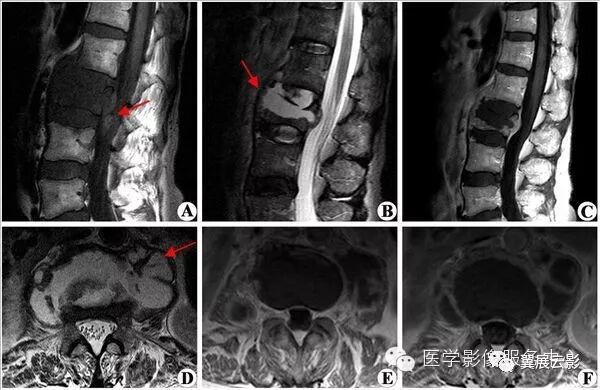

【MRI图片】:

【影像表现】:前列腺癌患者。T2WI(B、C、E)颈、胸、腰椎体及附件多发异常信号占位,部分病灶为低信号,部分为高信号;T1WI(A、D)显示病灶为低信号;增强扫描(F)病灶强化程度不一,部分强化明显。【影像诊断】:颈、胸及腰椎多发转移瘤。